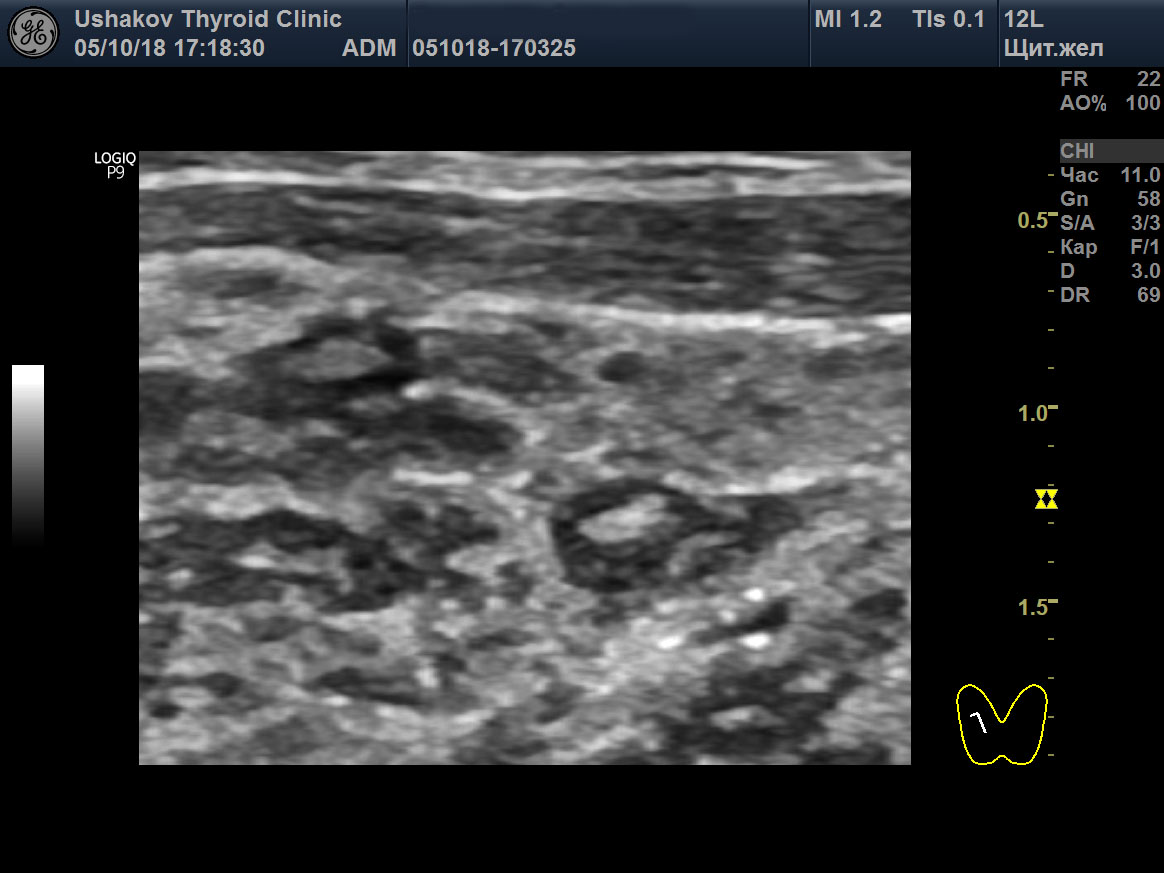

В последующем в дольке начинает происходить регенерация. Из стволовых клеток (или иначе) внутри лимфоидной ткани дольки появляется мелкий участок нормальной ткани щитовидной железы, который постепенно разрастается и заполняет объём дольки. Вместе с тем уменьшается количество лимфоидной ткани. При УЗИ эта фаза внутридольковой регенерации представляет собой разной величины гипер- или изоэхогенный участок внутри гипоэхогенной дольки (

рис. 2).

Рисунок 2 (начало) Правая доля ЩЖ пациентки 64 лет (поперечная, продольная проекции и увеличение; В-режим и ЭДК). Значительно выраженная внутридольковая регенерация в дольках с лимфоидной тканью. Фазы начальной и активной внутридольковой регенерации. Внутри гипоэхогенной (лимфоидной) ткани долек («лимфоидные дольки») определяются мелкие и крупные гипер- и изоэхогенные элементы регенерирующей ткани.